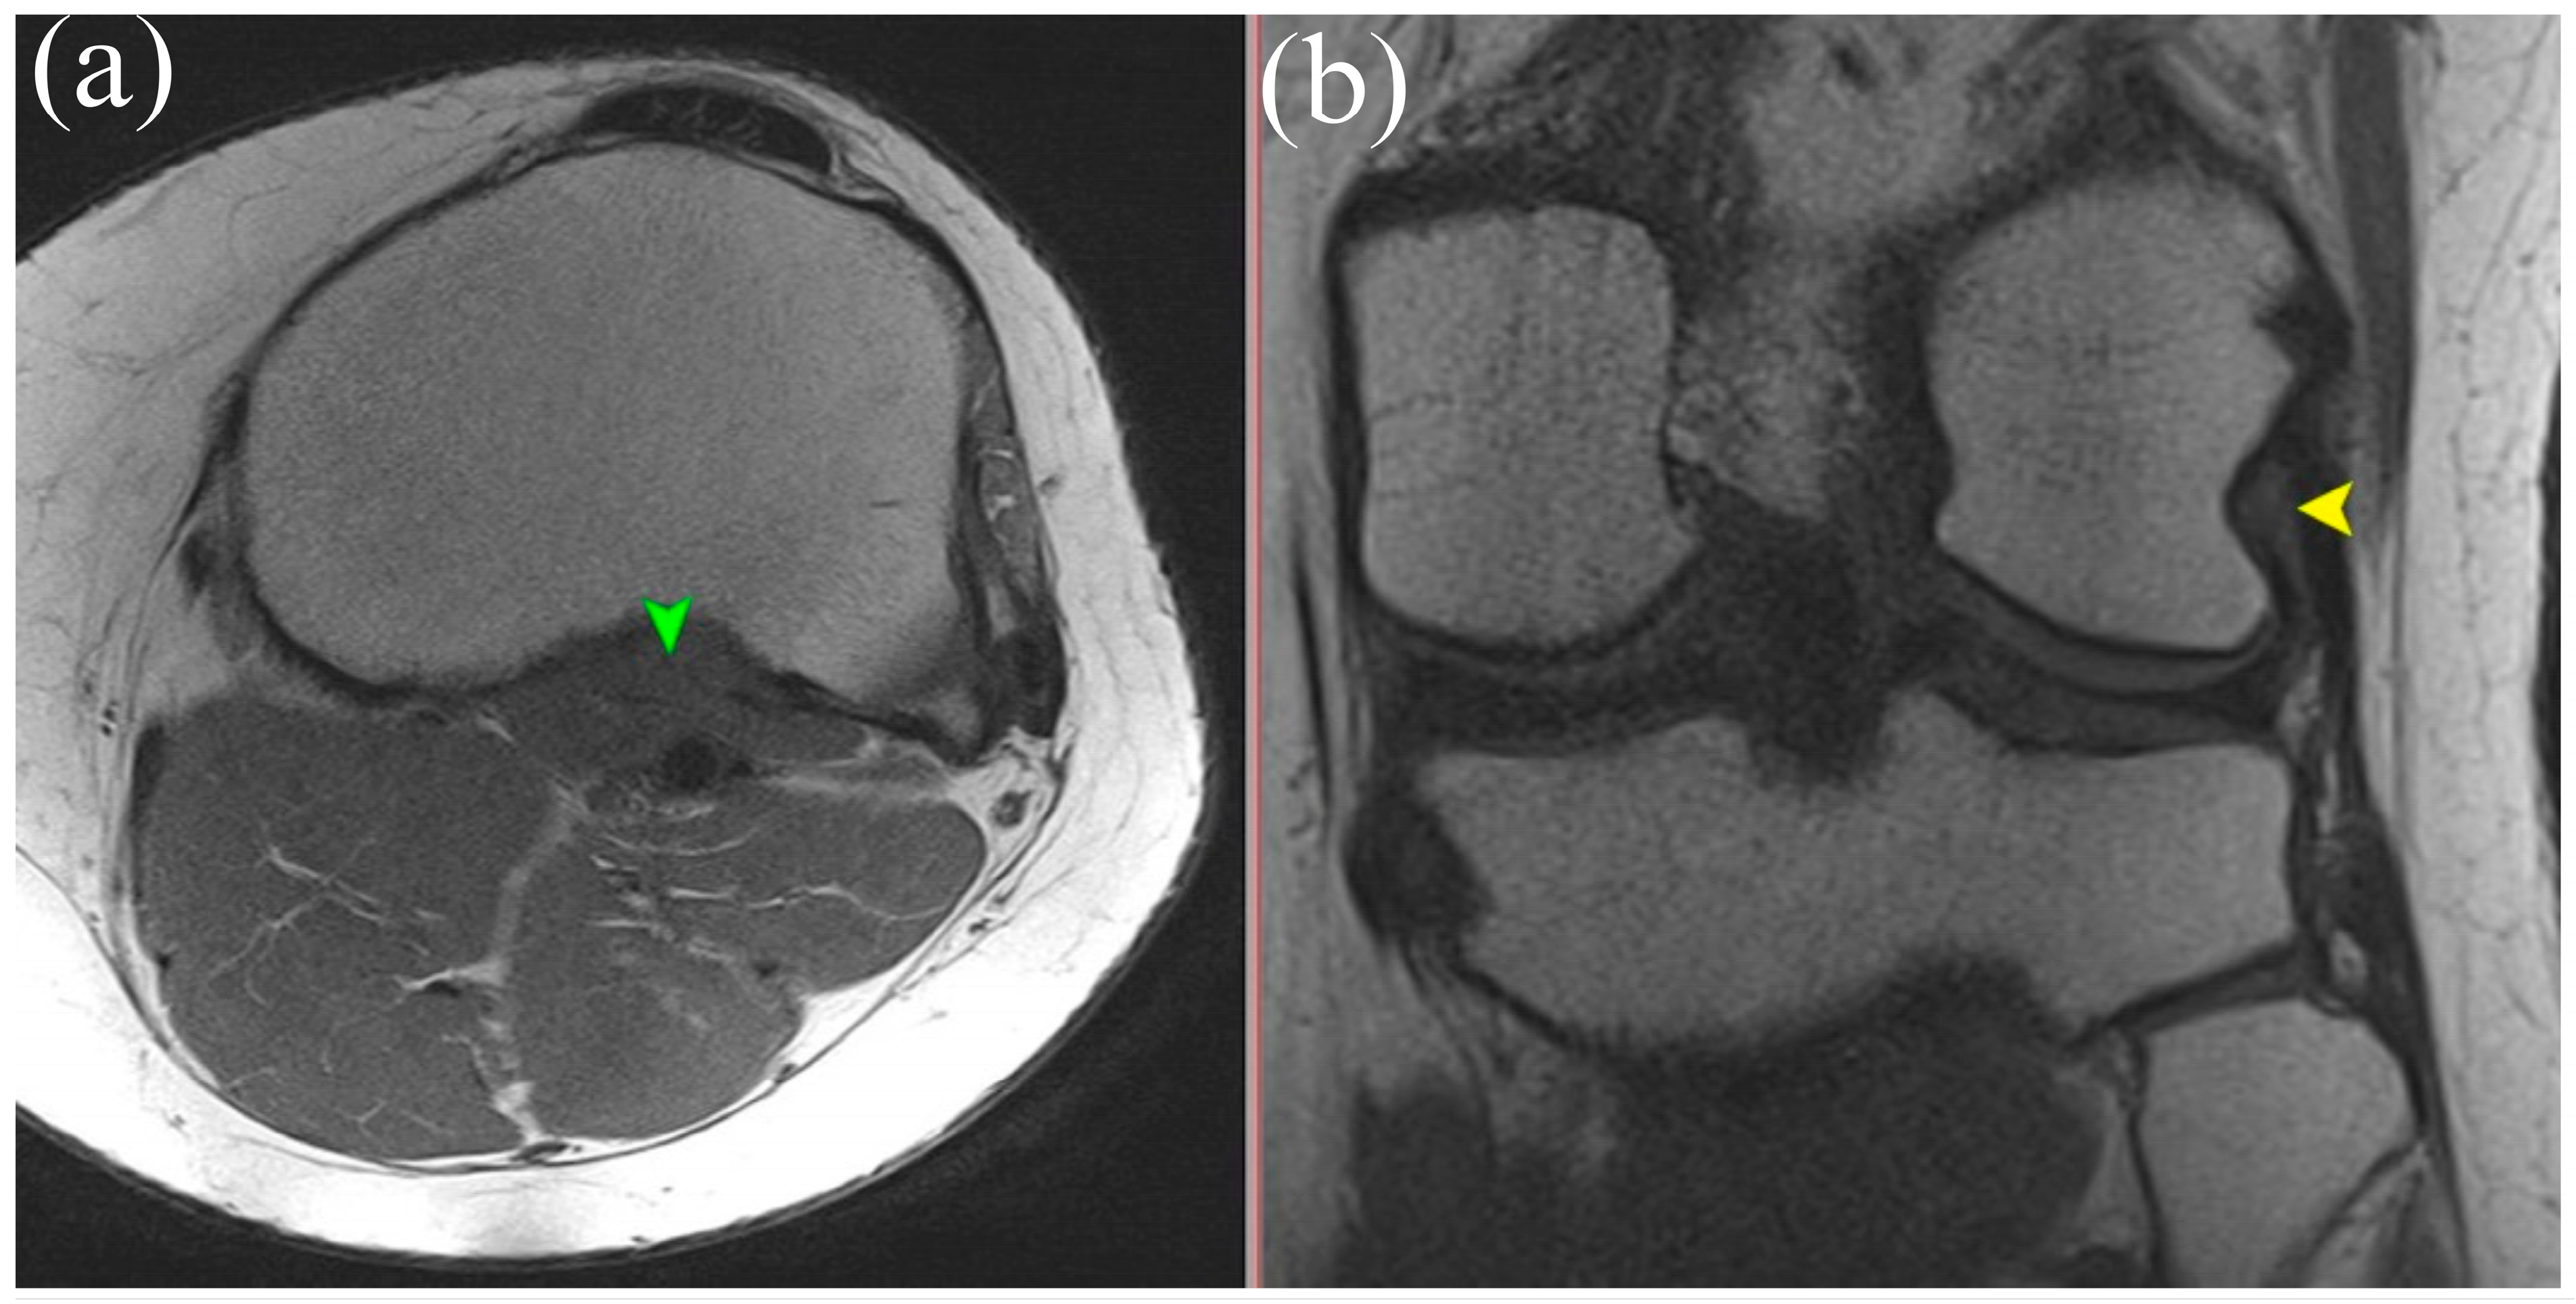

5.2. Magnetic Resonance Imaging (MRI)

5.3. High-Resolution Ultrasound (US)

- Advanced imaging (MRI and high-resolution ultrasound) should include targeted assessment of the PT, particularly for patients with lateral or rotational knee instability or for preoperative planning for complex reconstructions.